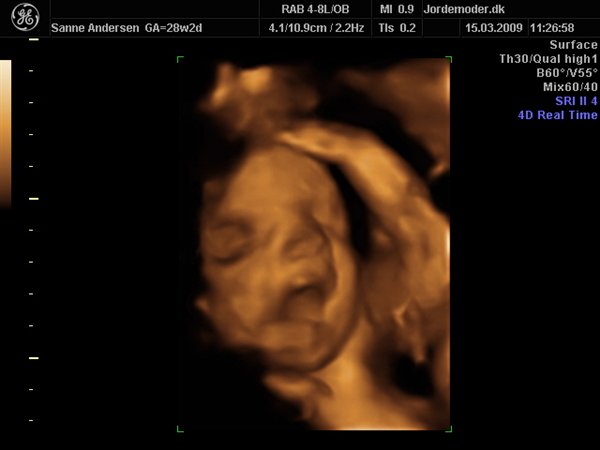

Det gik bare så godt til scanningen, men den ville meget heller sove end være aktiv så vi kunne få en masse forskellige billeder... men vi har fået en masse dejlige billeder og en dvd hvor der er masser af hjertelyd og rigtig pænt billede af hvordan hjertet slår

men vi venter en lille dreng, vi kunne desværre ikke få billede i 3d da han bare ikke ville rykke på sig og han lå så der var for meget fostervand...

Vedhæftede fotos (klik for at se i fuld størrelse)